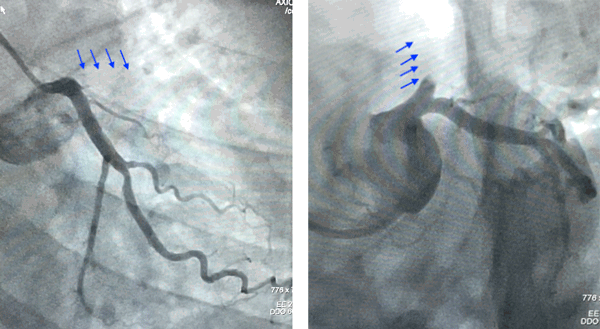

A 38 year old male with chest discomfort had a strongly positive stress perfusion scan. His coronary angiography showed a blocked lad artery.

This subset is called a Chroic Total Occlusion or a CTO. A hard tipped wire was used to cross the blockage and a Special Intravascular Ultrasound (IVUS) was used to get an image the blockage and to assess the size of the artery.

Based on this IVUS image, a large stent was deployed and the artery was opened and blood flow was restored.